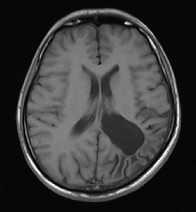

Figure 1: Brain tumour MRI: Magnetic resonance imaging (MRI) of the brain is a safe and painless test that uses a magnetic field and radio waves to produce detailed images of the brain and the brain stem. An MRI scanner consists of a large doughnut-shaped magnet that often has a tunnel in the center. Patients are placed on a table that slides into the tunnel. During the exam, radio waves manipulate the magnetic position of the atoms of the body, which are picked up by a powerful antenna and sent to a computer. The computer performs millions of calculations, resulting in clear, cross-sectional black and white images of the body. These images can be converted into three-dimensional (3-D) pictures of the scanned area. This helps pinpoint problems in the brain and the brain stem when the scan focuses on those areas [3].